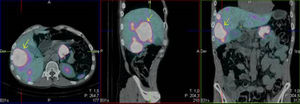

We present the case of a 52-year-old male investigated by dermatology for skin lesions. He was diagnosed with psoriasis vulgaris, but over the course of three years on treatment, without showing any improvement, he developed new lesions consisting of erythematous, erosive-crusted plaques on his lower limbs (particularly below the knees). A skin biopsy was requested as NME was suspected. The analysis showed psoriasiform dermatitis with compact parakeratosis and morphologically consistent subcorneal pustules and the patient was diagnosed with early-stage NME (Figs. 1 and 2). An abdominal CT scan was performed, finding a 3.2-cm mass in the body of the pancreas with lymphadenopathy in the coeliac trunk of a significant size and multiple liver metastases affecting both lobes. Blood tests showed normal blood glucose, haemoglobin 12.3g/dl (13.5–17.5), haematocrit 36% (41–53%), lutropin 12.5mIU/ml (1.5–9.3), follitropin 5.9mIU/ml (1.5–12.4), cortisol 14.3μg/dl (6.2–19.4), somatotropin 1.3ng/ml (<10.0), adrenocorticotropic hormone 87.8pg/ml (<46.0), enolase 29ng/ml (<16.0), beta-hCG 69mIU/ml (<3.0) and carcinoembryonic antigen 1.4ng/ml (<5.0). Investigations were completed with OctreoScan® (Fig. 3), which showed a large mass in the body of the pancreas measuring approximately 3cm, compatible with a glucagonoma, in addition to numerous areas of abnormal uptake of tracer in both lobes of the liver. Glucagonoma was diagnosed, which we decided to treat surgically, performing distal pancreatectomy with lymphadenectomy. The pathology report concluded that it was a well-differentiated G1 neuroendocrine tumour, compatible with glucagonoma of the body of pancreas, pT3 pN1. After surgery, the patient made good progress and, two weeks after the intervention, the skin lesions had completely disappeared (Fig. 4). The patient is currently on treatment with lanreotide and is awaiting assessment for liver transplantation.

Glucagonomas can be detected by CT, MRI or ultrasound.4 As they express somatostatin receptors, scintigraphy with somatostatin analogues is used to demonstrate the presence of the cancer and the extent to which it may have spread.